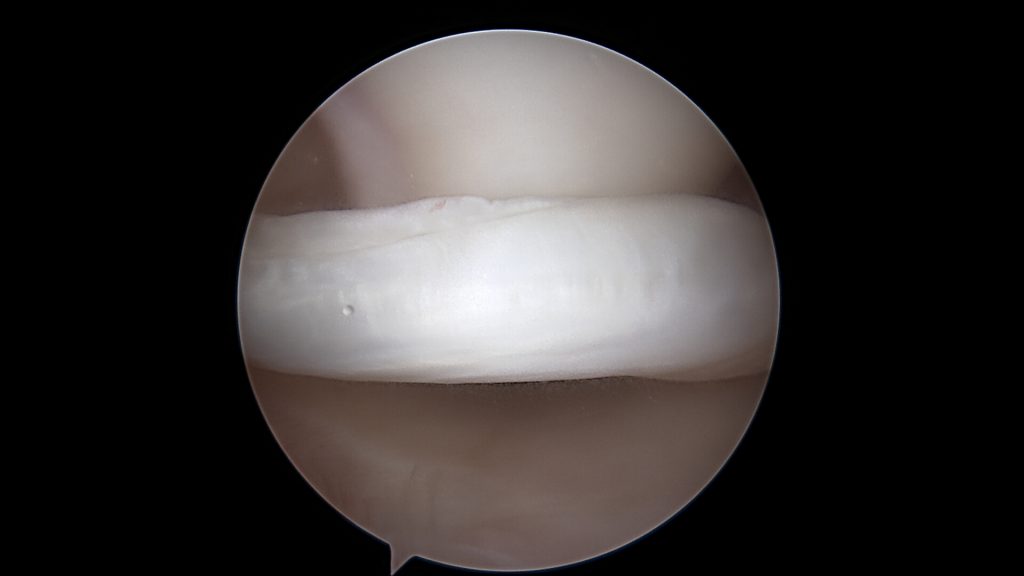

W stawie kolanowym występują dwie łąkotki, przyśrodkowa oraz boczna. Spełniają one w nim kilka ważnych funkcji. Rozkładają siły nacisku jakie wywiera kość udowa (o obłym kształcie) na kość piszczelową (względnie płaską). Są częściowo powierzchnią ślizgową w stawie. Biorą udział w jego stabilizacji biernej oraz czynnej poprzez zawarte w nich receptory czucia głębokiego. Zbudowane są z tkanki łącznej chrzęstno-włóknistej. Łąkotka przyśrodkowa jest zbliżona kształtem do litery C a boczna do litery O.

Ponieważ spełniają one ważne funkcje, a ich uszkodzenie czy zniszczenie może doprowadzić do dalszej destrukcji kolana z całkowitym zniszczeniem stawu (zaawansowana choroba zwyrodnieniowa) należy w jak największym stopniu je zachować. Stąd przewodnią myślą w chirurgii łąkotek jest „save the meniscus” – zachowaj łąkotkę.